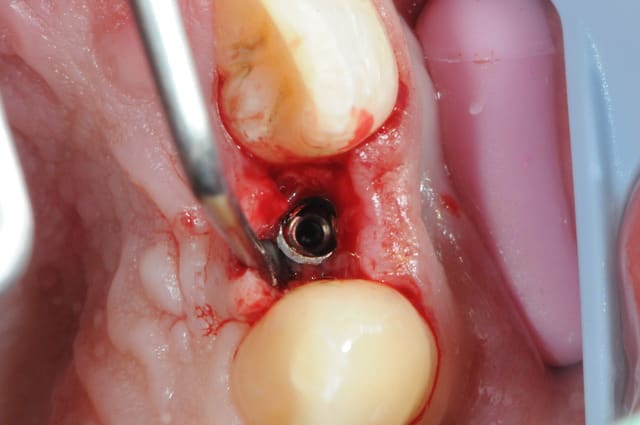

je reviens sur ce cas que j'ai un peu délaissé...

-cicatrisation

-mise en place vis de cica petit diamètre

-ensuite on augmente le diamètre en conservant et en gonflant les tissus gingivaux